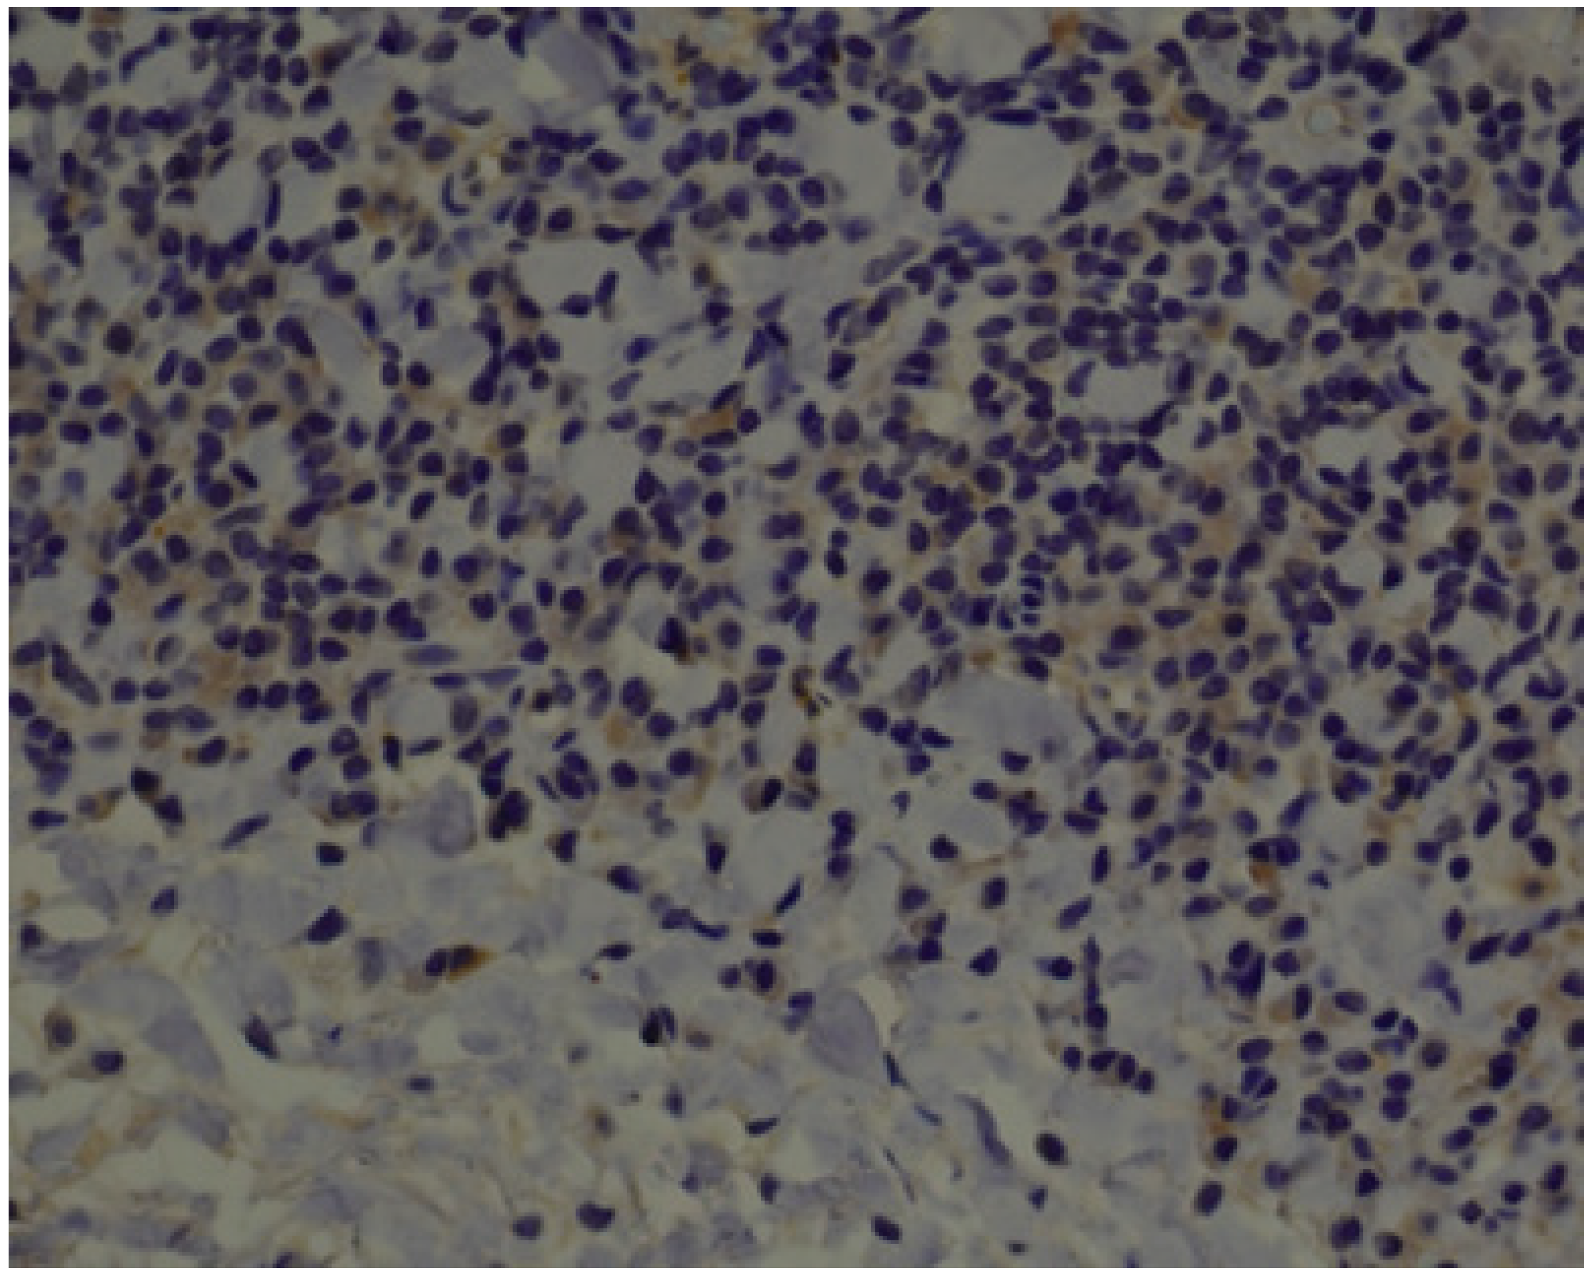

3.1. Histopathology and Immunohistochemistry